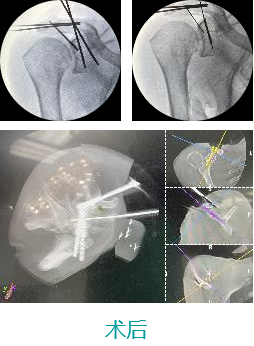

天玑II 辅助肩胛骨骨折切开复位内牢靠术

基本情形:患者男,,,,,,,,52岁,,,,,,,,肩锁枢纽脱位,,,,,,,,肩胛骨骨折

机械人辅助优势:天玑II可与种种术中影像装备配合,,,,,,,,为各部位骨折术式提供精准定位

病例泉源:北京积水潭医院